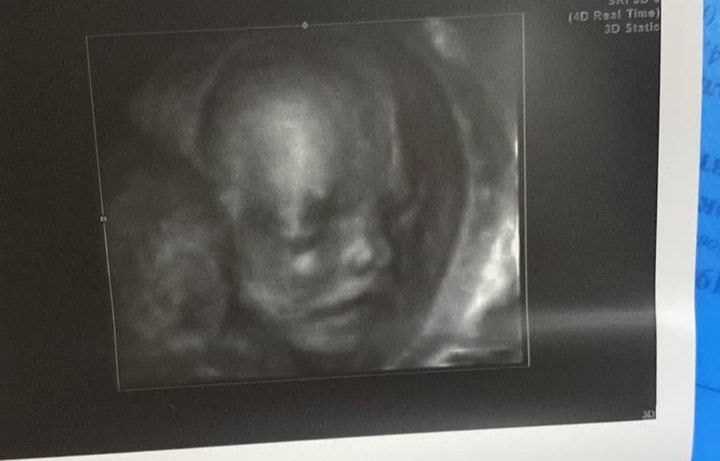

Изображение вот 28-29